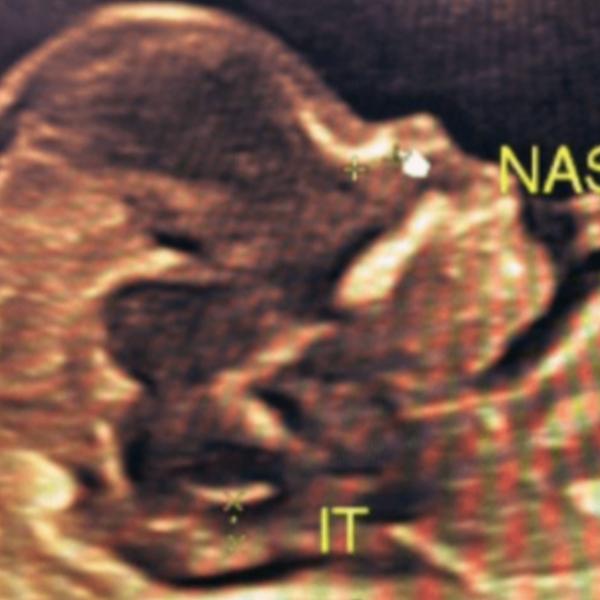

View DetailsNt nb scan in rohini delhi Nuchal Translucency (NT...